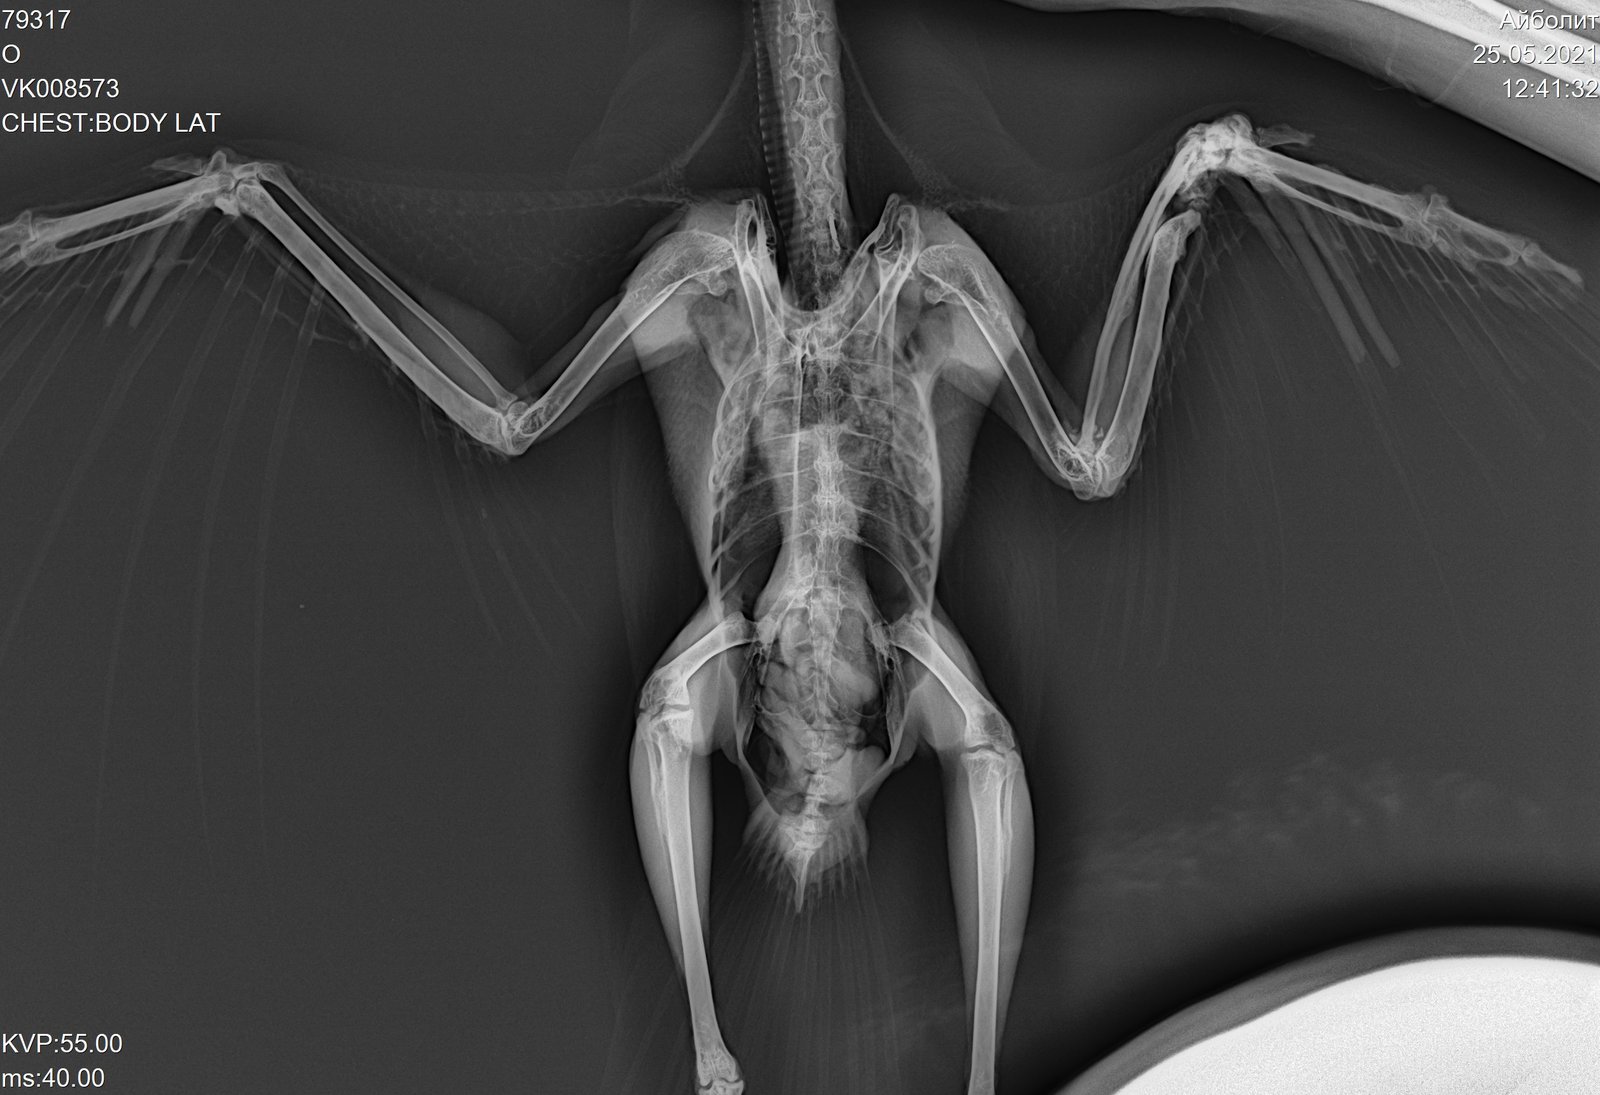

Получила выписку и рентген. Прикрепляю последние снимки.

VK008573_1.jpg

VK008573_2.jpg

VK008573_3.jpg

VK008573_4.jpg

На рентгене нет ли перелома заднего пальца?

@fishka врач не увидела, но мне увиделся перелом. И не на рентгене, а в живую. Палец гнется не в ту сторону :(